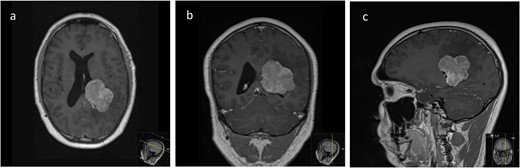

We hereby present the case of a 32-year-old gentleman referred to the neuro-oncology service with an 8-months history of left sided headaches, dizziness, and blurred vision. MRI head demonstrated a 50 × 52 × 51 mm lesion in the posterior horn of the left lateral ventricle, with extension into the periventricular white matter (Fig. 1). Following multi-disciplinary discussion, a plan was made for the patient to undergo a minimally invasive approach for resection of this lesion. Pre-operative cortical and subcortical mapping was performed with navigated transcranial magnetic stimulation (nTMS) and diffusion tensor imaging (DTI). The best trajectory was defined taking into consideration the localization of the cortico-spinal tract (CST, red), the inferior fronto-occipital fasciculus (IFOF, green) and the optic radiations (OR, yellow) (Fig. 2).

Pre-operative axial (a), coronal (b), and sagittal (c) T1-weighted post contrast MRI sequences demonstrating the avidly enhancing lesion in the posterior horn of the left lateral ventricle, with extension into the periventricular white matter.